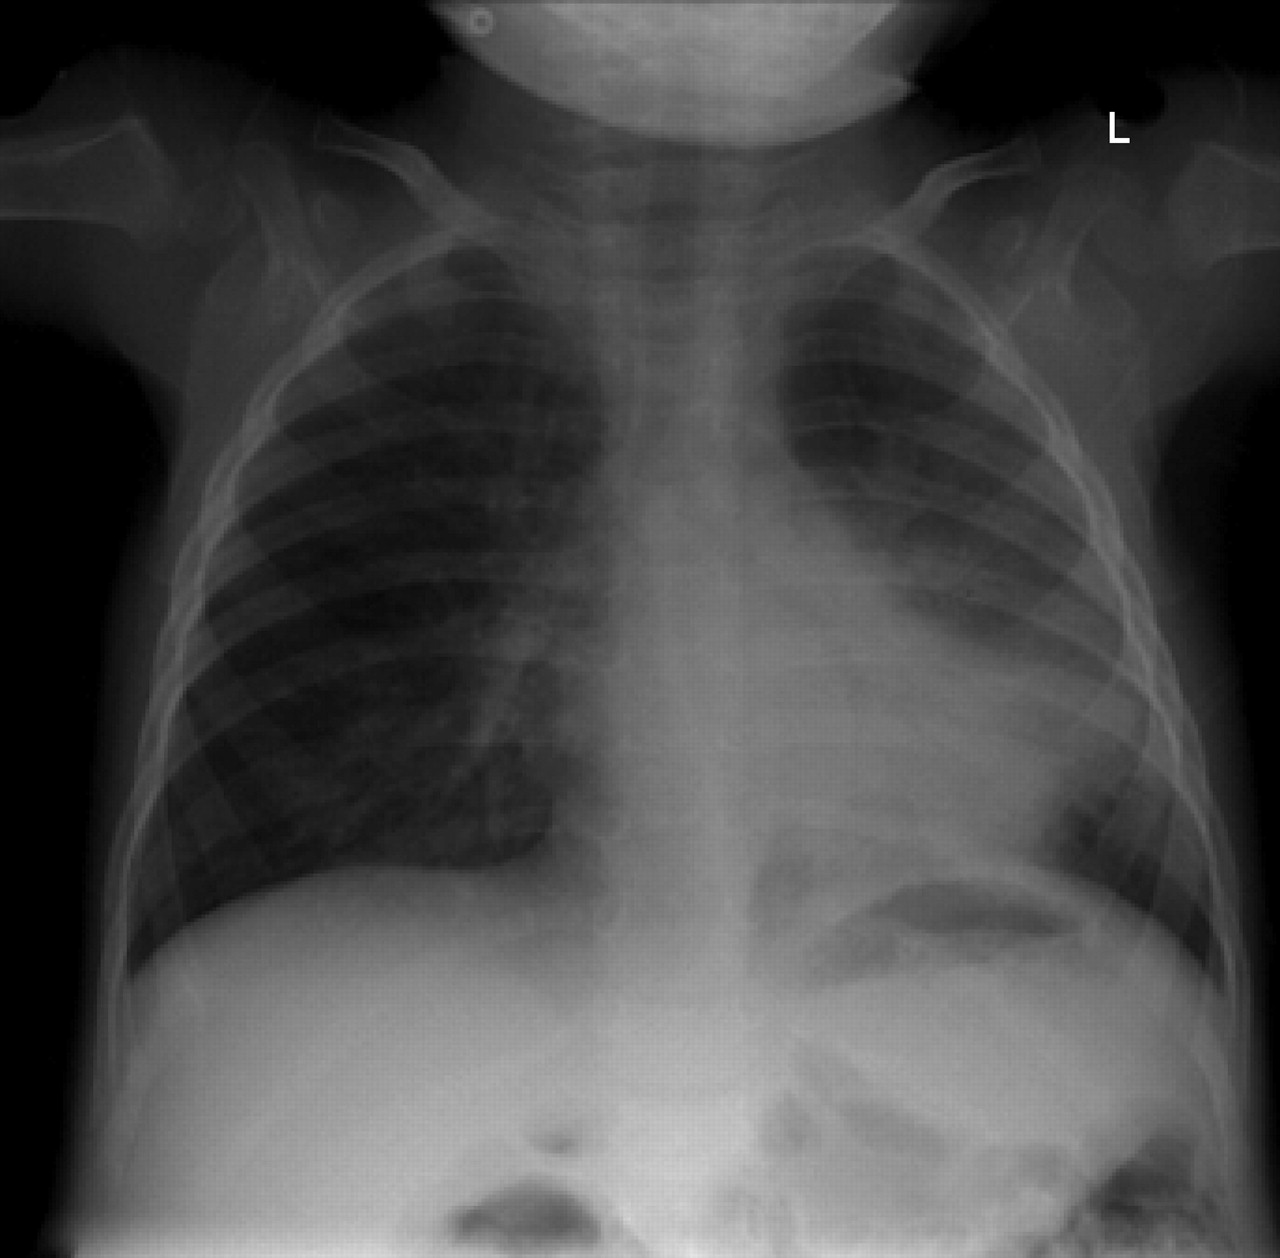

For this type of pneumonia performing a chest x-ray on the. Chest x-rays can reveal areas of opacity seen as white which represent consolidation. In complicated cases of pneumonia perform chest radiography 6 weeks after treatment to verify resolution of the pneumonia and to screen for any underlying predisposing.

Baby chest x ray pneumonia Thursday March 24 2022 Respiratory syncytial virus or RSV most commonly seen in children under age 5 Parainfluenza virus. Pneumonia is not always seen on x-rays either because the disease is only in its initial stages or because it involves a part of the lung not easily seen by x-ray. An important test for making a diagnosis of pneumonia is a chest x-ray.

This chest X-ray shows an area of lung inflammation indicating the presence of pneumonia. However chest X-ray examinations for pneumonia detection are prone to subjective variability 2 3. Please see disclaimer on my website.

It determines the pathogen that could have caused pneumonia. The differential for the radiologic finding of pulmonary consolidation includes blood pulmonary hemorrhage pus infection ie. We investigate whether chest radiographic findings could be used as predictors of severity of childhood pneumonia.